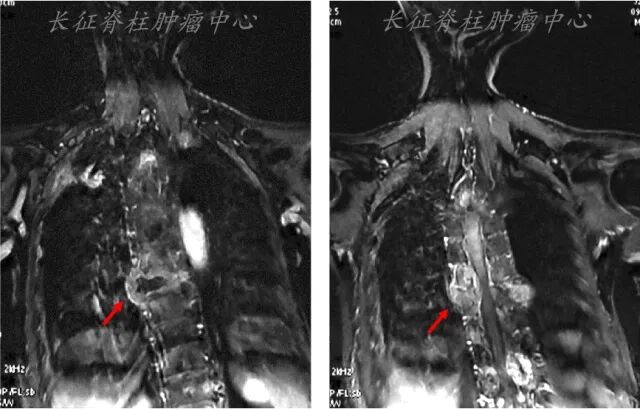

2021.01.05查全脊柱MRI示:胸6-7转移瘤伴硬膜囊明显受压;

MRI:胸5-9椎体信号异常,T7椎体压缩骨折,T4-8椎管内占位。

图2. MRI检查结果